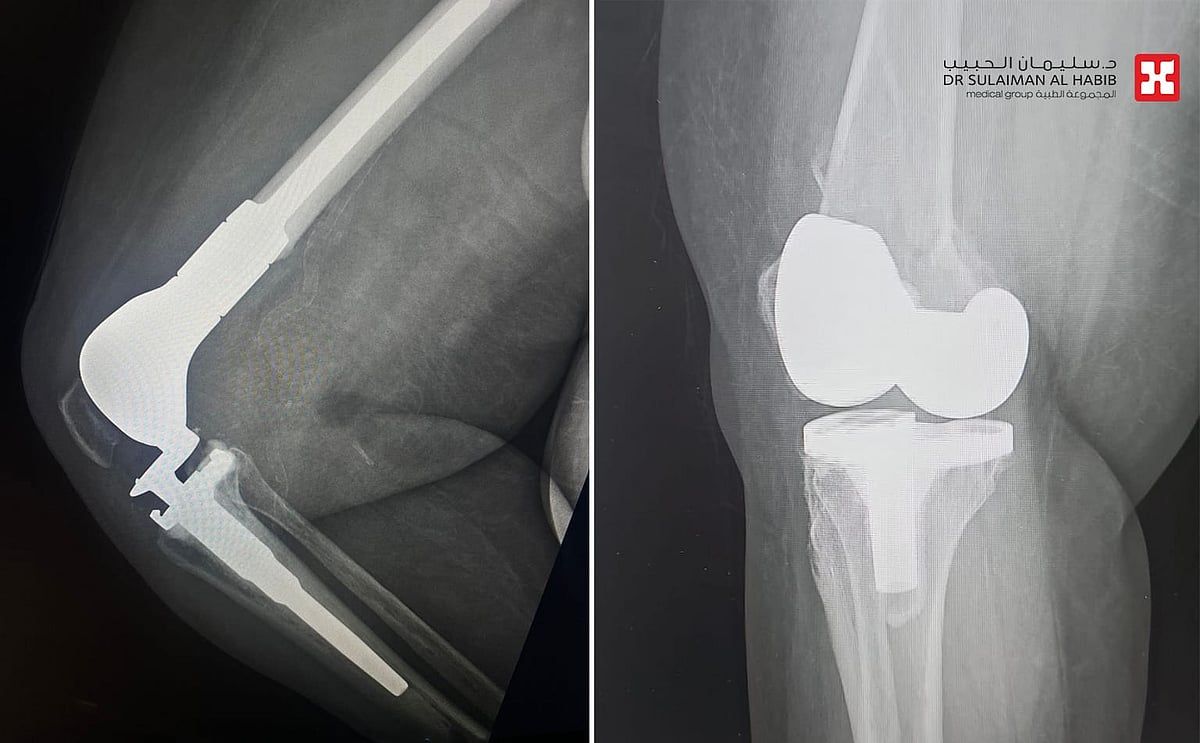

الذي قال أن السيدة حضرت إلى المستشفى وهي تشتكي من آلام حادة وتورم بالطرف السفلي الأيمن، مع عدم القدرة على الحركة والتحمل، إضافة إلى أمراض مزمنة كالشريان التاجي وداء السكري وارتفاع ضغط الدم، وخضعت لفحوصات دقيقة، حيث أظهرت صور الأشعة الطبية كسراً في نهاية عظم الفخذ حول المفصل الصناعي، وتبين عدم قابلية الكسر للتثبيت بالصفائح أو البراغي، بالنظر إلى هشاشة عظام المراجعة وتقدم عمرها، فتم تبني خطة علاجية تناسب الحالة، وأجريت لها عملية جراحية تم فيها استبدال الجزء السفلي من عظمة الفخذ، في تدخل جراحي استمر لـ"4" ساعات، وتكللت ولله الحمد بالنجاح التام، ونقلت المراجعة إلى جناح التنويم.